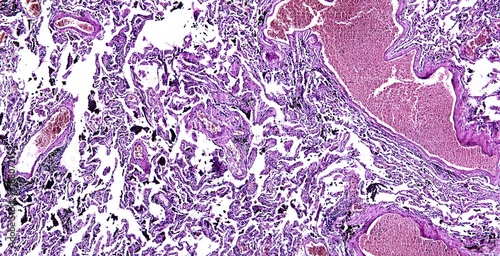

Mikrofotografi - Plakater, Poster, Billeder på lærred